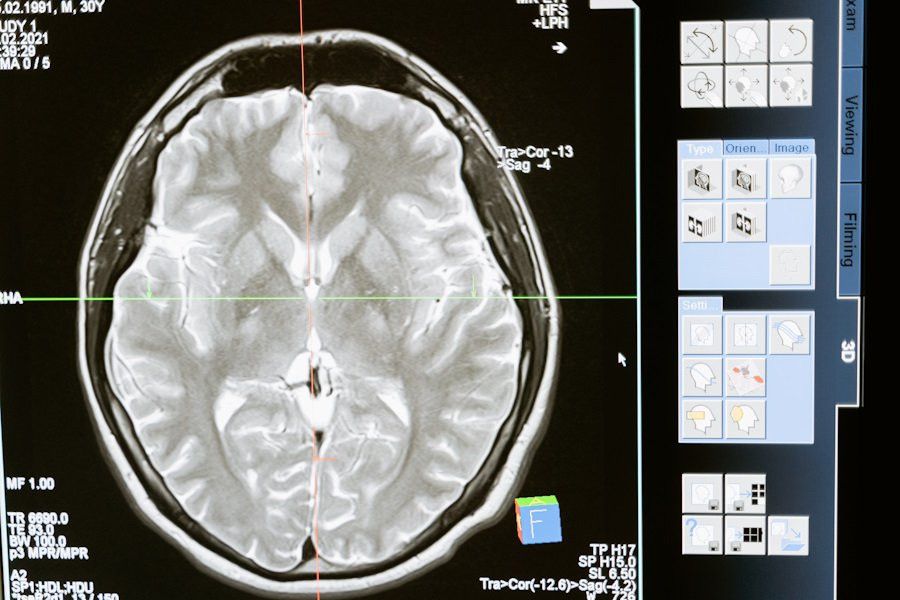

Учёными National Institute on Aging (США) проведено исследование для выявления связей определенных белков с возникновением деменции — состояния, при котором ухудшаются память и поражается мозга человека. Исследование может стать базой для разработки новых методов диагностики и лечения заболеваний, вызывающих деменцию. Доклад о работе обнародован на портале  Science Translational Medicine.

Ученые выявили 32 белка, регуляция которых в возрасте от 45 до 60 лет была сильно связана с возможностью развития деменции в пожилом возрасте. Некоторые из этих белков играют важную роль в мозге, но большинство выполняют другие функции в организме.

Особый интерес вызвали белки, связанные с процессом протеостаза — это контролирующий механизм, который балансирует уровень белков в организме. Этот механизм важен для предотвращения скопления белков в мозге, что часто наблюдается у людей с болезнью Альцгеймера, наиболее распространенным видом деменции.